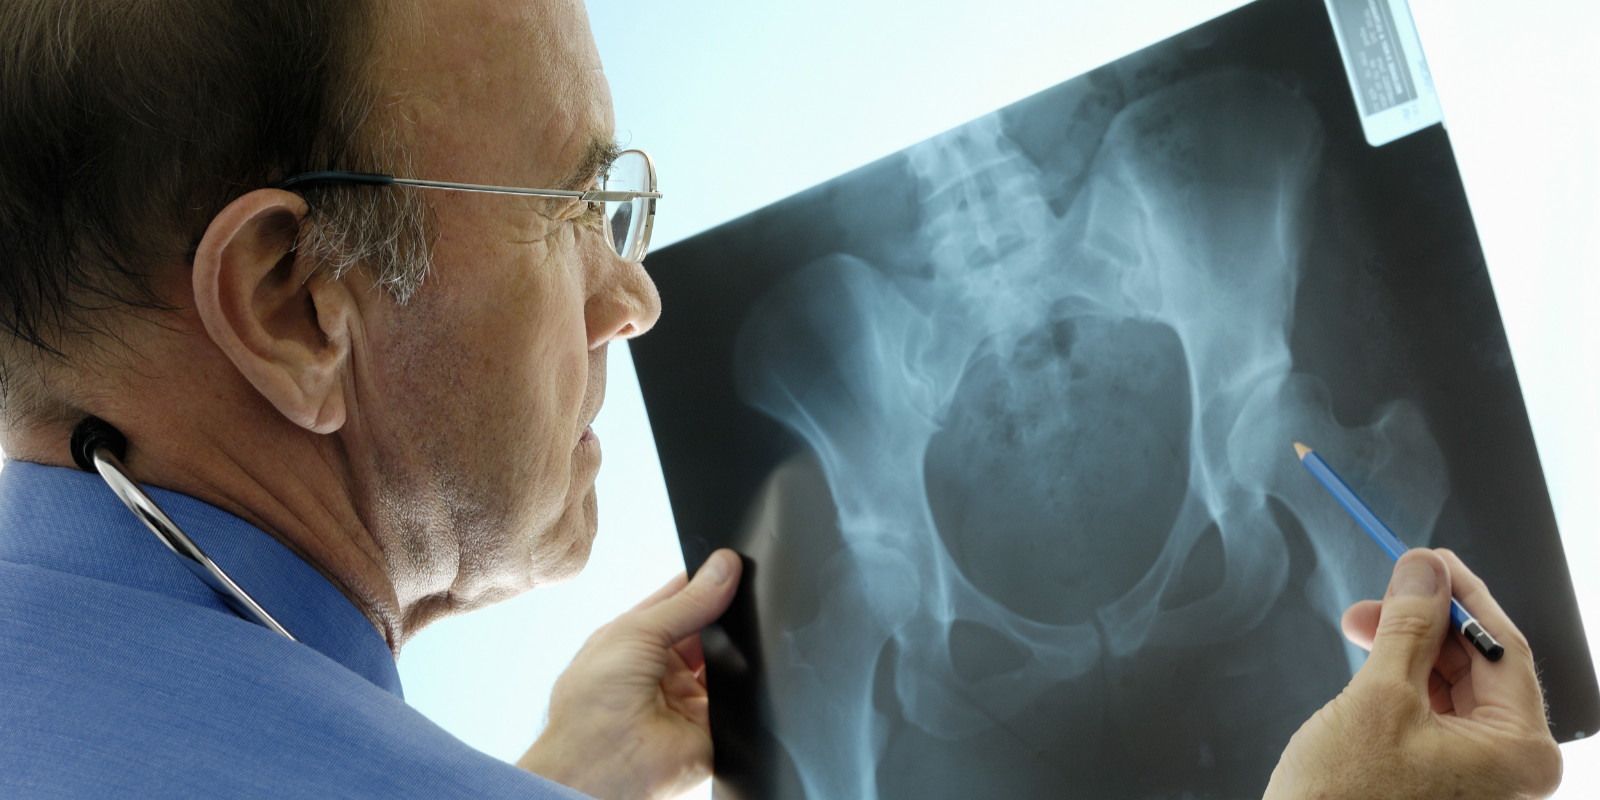

首先,我们我们需要先了解一点;在我们全身206块骨头中,不同部位的骨骼的愈合时间是不同的。举例子说,对于老年人的股骨颈部位的骨折,很难自行愈合,往往需要通过外科手术的方式辅助帮助其恢复其功能。对于小孩子比较常见的前臂青枝骨折,可能仅仅需要1个月的时间就能长好。

1,局部血液供应:如果骨折部血液供应好,则骨折愈合快,如肱骨的外科颈(上端)骨折;反之,局部血液供应差者,骨折愈合慢,如股骨颈骨折。骨折类型也和血液供应有关:如螺旋形或斜形骨折,由于骨折部分与周围组织接触面大,因而有较大的毛细血管分布区域供应血液,愈合较横形骨折快。